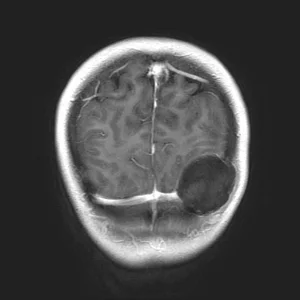

December 20, 2012. I don't think anyone in my life, except for me, remembers this actual date. It was the day I had brain surgery on a tumor that had taken residency in the back left corner of my brain. (Yes, that ball in the image is the tumor). I wake up each year on the anniversary thankful, reflective and a little sad, because I remember what I had to go through - the subconscious fear before the surgery, the pain after and really, the pain I still feel from it every day.

The diagnosis was an epidermoid tumor that had gotten so big it had eaten through my skull (gross), but that is why you could feel it on the back of my head - there was no skull left to cover it. Panic set it and I started seeing neurosurgeons in Dallas and New York.  I ultimately decided that I would have surgery in Dallas and had a neurosurgeon in New York ready for me should I need anything in the long term.